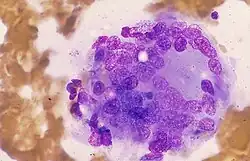

Histologie

Das histologische Bild der subakuten Thyreoiditis ist durch eine granulomatöse Entzündung und das Vorliegen von Riesenzellen geprägt. Die Granulome bestehen neben den Riesenzellen aus abgestorbenen Zellen (Zellnekrosen) und Makrophagen. Im Rahmen der Entzündungsreaktion kommt es zu einer Zerstörung der Follikelepithelzellen der Schilddrüse und zum Austritt von Kolloid, das durch die Riesenzellen phagozytiert wird. Die Granulome treten im Schilddrüsengewebe nur an einigen Stellen auf. Das restliche Schilddrüsengewebe erscheint unversehrt.[17]